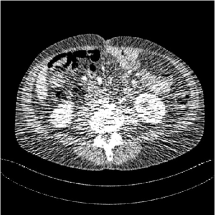

III.C. Low-dose Experiments with Mayo Clinic Data

First, we study transform training based on Mayo Clinic data. As shown in Fig. 6, seven slices obtained at regular dose from three patients are used for transform learning. The number of pixels . Similar to the phantom experiments, overlapping patches are extracted with a patch stride. The number of overall training patches is about . We set for ST, , , for MARS2, , , , , for MARS3, , , , , , , , , for MARS5, , , , , , , , , , , , , for MARS7. The iteration number in Algorithm 1. Fig. 7 illustrates the learned transforms obtained with Mayo Clinic data. Different from the XCAT phantom case, these transforms up to MARS5 display more complex features and structures. The rich features of the MARS models better sparsify the training images over layers compared to the single-layer model (ST).

![]()